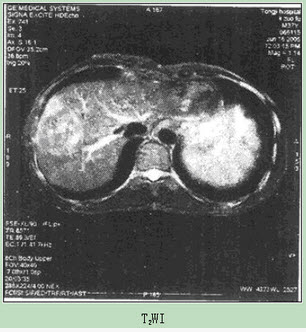

患者男性,54岁,体检发现肝脏占位,MR图像如下,最有可能的诊断是()。

A:肝癌

B:肝肉瘤

C:肝血管瘤

D:肝腺瘤

E:肝再生结节